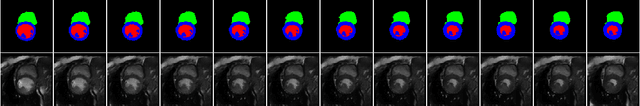

Abstract:We propose a method for synthesizing cardiac MR images with plausible heart shapes and realistic appearances for the purpose of generating labeled data for deep-learning (DL) training. It breaks down the image synthesis into label deformation and label-to-image translation tasks. The former is achieved via latent space interpolation in a VAE model, while the latter is accomplished via a conditional GAN model. We devise an approach for label manipulation in the latent space of the trained VAE model, namely pathology synthesis, aiming to synthesize a series of pseudo-pathological synthetic subjects with characteristics of a desired heart disease. Furthermore, we propose to model the relationship between 2D slices in the latent space of the VAE via estimating the correlation coefficient matrix between the latent vectors and utilizing it to correlate elements of randomly drawn samples before decoding to image space. This simple yet effective approach results in generating 3D consistent subjects from 2D slice-by-slice generations. Such an approach could provide a solution to diversify and enrich the available database of cardiac MR images and to pave the way for the development of generalizable DL-based image analysis algorithms. The code will be available at https://github.com/sinaamirrajab/CardiacPathologySynthesis.